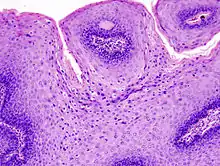

Micrograph of a genital wart with the characteristic changes (parakeratosis, koilocytes, papillomatosis). H&E stain.

The diagnosis of genital warts is most often made visually, but may require confirmation by biopsy in some cases.[18] Smaller warts may occasionally be confused with molluscum contagiosum.[17] Genital warts, histopathologically, characteristically rise above the skin surface due to enlargement of the dermal papillae, have parakeratosis and the characteristic nuclear changes typical of HPV infections (nuclear enlargement with perinuclear clearing). DNA tests are available for diagnosis of high-risk HPV infections. Because genital warts are caused by low-risk HPV types, DNA tests cannot be used for diagnosis of genital warts or other low-risk HPV infections.[3]